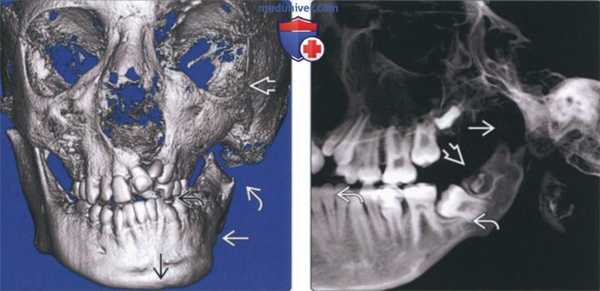

(Слева) На трехмерной реконструкции (КЛКТ, вид спереди) у мальчика 12 лет с гемифациальной микросомией III типа определяется врожденное отсутствие мыщелка и передней части ветви. Наблюдается задержка формирования левой половины нижней челюсти, левая глазница увеличена в размерах. Костная срединная линия нижней челюсти смещена влево, окклюзионная плоскость приподнята.

(Справа) На панорамной реформатированной КЛКТ определяется отсутствие мыщелка, уменьшение высоты тела нижней челюсти. В ветви видны формирующиеся зубы.